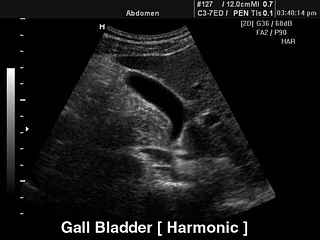

УЗИ желчного пузыря.

Tissue Harmonic Imaging (2-я гармоника).